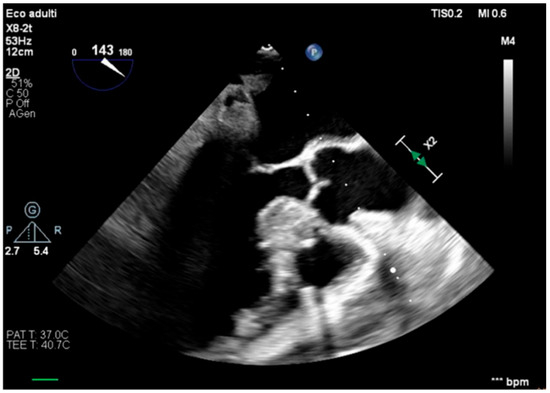

We describe a case of a 75-year-old woman affected by a post-myocardial-infarction ventricular septal defect (VSD) and a left-ventricle (LV) apical aneurysm. The patient underwent surgery for VSD closure and aneurysm exclusion. The patient had a STEMI (ST-elevation myocardial infarction), with evidence of occlusion of the anterior interventricular artery, for which thrombus aspiration and stenting of the left coronary artery and proximal anterior interventricular artery was performed. Then, she developed cardiogenic shock with pulmonary edema and thus required the support of an IABP (intra-aortic balloon pump) of C-PAP and levosimendan in continuous infusion for 24 h. Seven days after the event, a large post-infarct VSD at the apical level with a left–right shunt occurred. She was therefore transported from the spoke center to our hospital and underwent surgical treatment, namely, post-infarct VSD closure and exclusion of a left ventricular aneurysm. The intra-operative transesophageal echocardiography showed concentric LV remodeling, slight dilatation, LVEF 28% (Figure 1), and akinesia of the mid-apical segments in toto with aneurysmal evolution (Figure 2).

Figure 2. Trans-gastric view, apical level (short axis).